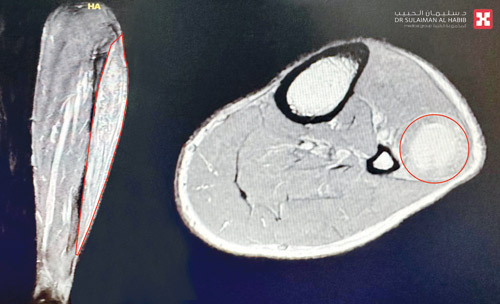

وأوضح أن نتائج الفحوصات أكدت وجود فجوة واضحة في العضلة الشظوية الطويلة للساق، وصعوبة تحريك القدم اليسرى إلى الأعلى، بالإضافة إلى وجود تجمع دموي موضعي تسبب في حدوث ضغط شديد على العصب الشظوي، مما أدى إلى «سقوط القدم»، بالإضافة إلى وجود قطع طولي كبير في العضلة الشظوية الطويلة.

وأفاد البروفيسور الجاسر أن الفريق الطبي عقب انتهائه من دراسة كامل الفحوصات قرر التدخل الجراحي، وقد أجريت العملية للمريض واستغرقت 4 ساعات، وتم فيها إزالة التجمع الدموي المسبب للضغط على العصب الشظوي وتحريره، مع التأكد من عمله أثناء الجراحة باستخدام أدوات خاصة لتحفيز تلك الأعصاب، تبع ذلك إصلاح القطع في العضلة الشظوية الطويلة، نقل بعدها المريض إلى جناح التنويم.